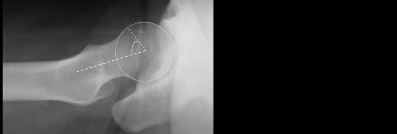

A 72-year-old female presents with progressive left thigh and knee pain for the last year. 5 years ago she sustained a femoral neck fracture treated with the implant seen in Figures A-C (current radiographs). The thigh pain is worse with weight-bearing. C-reactive

protein and erythrocyte sedimentation levels are within defined limits. Which of the following is the most likely cause of her pain?